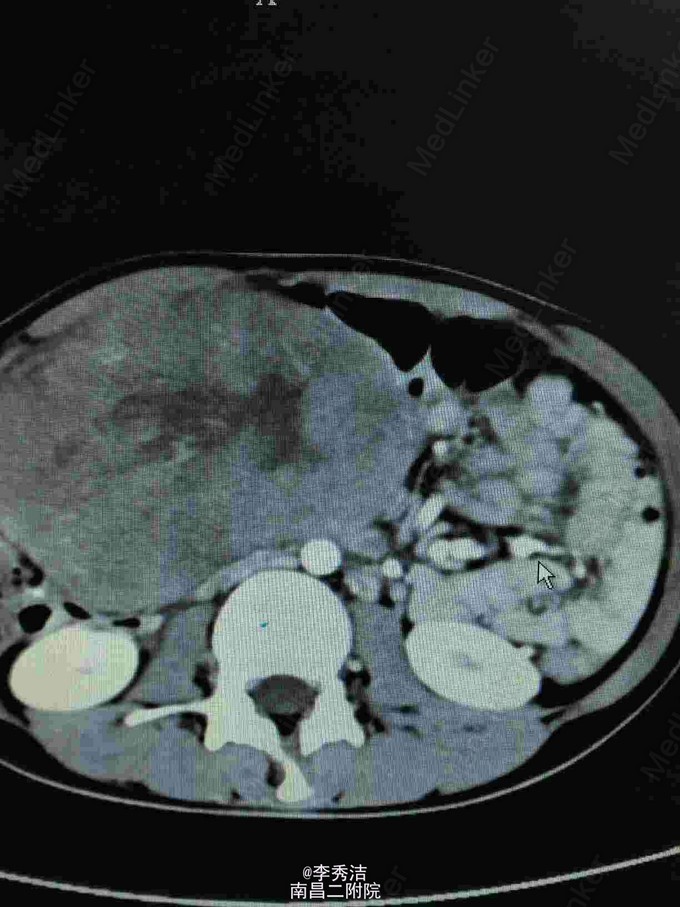

查体:中下腹部明显彭隆,未见肠型及蠕动波,未见腹壁静脉曲张,腹肌软,下腹部可触及约20*20cm包块,质硬,活动度差,叩诊实音,肝脾肋下未及,妇科检查:外阴:已婚未产式;阴道:畅软,少量白色分泌物;宫颈:少糜,宫体及双附件因盆腔巨大包块扪诊不清。血清HCG70.1mIU/ml。腹部CT示腹盆腔内见一巨大包块影,大小约16*8.1cm,增强扫描示不均匀增强,腹腔、盆腔内见积液,结合血清HCG,不排外生殖系统恶性肿瘤可能。彩超示:子宫上方巨大包块,不排除来源于附件可能,子宫、显示不清。双侧附件

诊断:腹腔包块性质待查,在全麻下行剖腹探查术,腹腔见淡黄色腹水约100ml,子宫色泽及形态无异常,左侧附件无异常,右侧卵巢见一大小约30*25cm囊肿,右侧输卵管附着于包块上,大网膜见两个绿豆大小结节,包块表面见血管丰富,术中出血较多,遂行右侧附件切除。送术中冰冻示:无性细胞肿瘤,考虑患者处于Ia期, 遂行双侧附件切除+双侧盆腔淋巴结清扫+大网膜切除术,手术顺利。术后诊断:卵巢无性细胞瘤 Ia期。